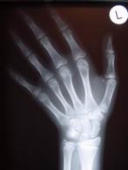

Die Früherkennung von Haltungsfehlern und Gelenkerkrankungen im Kindesalter stellt eine wichtige Voraussetzung zur Vorbeugung und Verhütung orthopädischer Beschwerden im späteren Alter dar. Zu den Untersuchungen zählen u.a. die Feststellung eventueller Haltungs- und Gangbildauffälligkeiten, die Beurteilung der Fußstatik zur frühzeitigen Vermeidung von Spätschäden sowie die Behandlung von akuten Gelenkbeschwerden. Sportmedizinische Beratung für Kinder Endgrößenbestimmung Durch die Röntgenaufnahme der linken Hand ist es bei Kindern ab dem 6. Lebensjahr möglich, die zu erwartende Endkörpergröße zu bestimmen und ggf. frühzeitig bei Riesen- oder Minderwuchs therapeutisch einzugreifen.